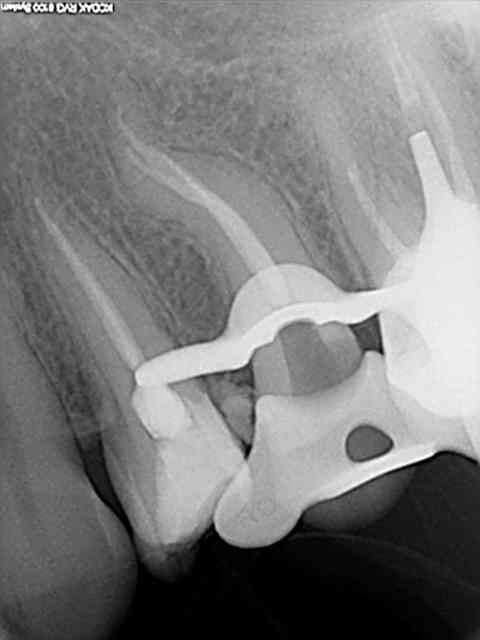

Voici un cas de fracture compacteur.

Utiliser un mac spaden dans ce genre de cas était une bêtise.

Aprés beaucoup d'efforts pour perméabliser les 2 cannaux et les préparer, c'est trop dommage de gacher le résultat en cassant un compacteur.

Cela ne m'a pas gêné pour desobturer et faire l'empreinte pour l'inlay-core, mais la condensation de la gutta au niveau apical n'a pas été terrible.

C'est d'ailleurs un des cas qui m' a décidé à utiliser de temps en temps le thermafill.